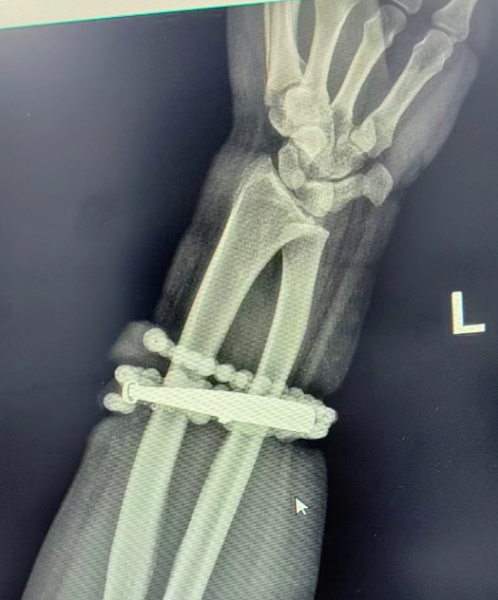

然而,就在两周前,龚女士的情况急转直下:手腕不仅疼痛加剧,还出现了明显的红肿,甚至有脓液渗出。她这才惊觉——手镯和串珠,已经有一部分“长”进了肉里,根本取不下来了!

“这是典型的首饰长期压迫、摩擦,加上细菌感染,引发的慢性炎症和肉芽组织增生。”医生介绍,此时,手镯和串珠已经成了一个不断刺激皮肤、污染伤口的“病灶”,如果不尽快手术取出,感染可能进一步扩散,甚至危及生命或影响手臂功能。

经过一个多小时的手术,医生们将手镯和串珠从厚厚的增生组织中完整剥离出来。目前,龚女士恢复良好,已顺利出院。